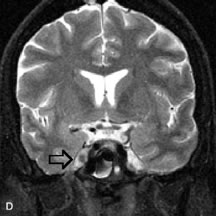

Fig. 14. Patient with Ehlers-Danlos syndrome who presented with abrupt onset of severe proptosis. A-C. Postcontrast fat-suppressed T1-weighted MR scans demonstrate marked proptosis and engorgement of the extraocular muscles and superior ophthalmic vein (arrows). D. T2-weighted scan through the cavernous sinus demonstrates enlargement and arterialized flow void within the right cavernous sinus (open arrow).